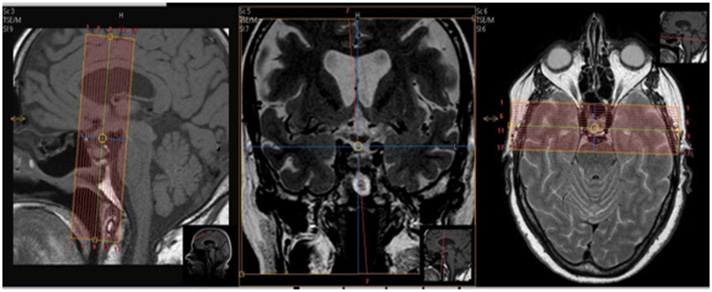

| SAG | T1 FAT SAT | TSE | 2mm | 0mm | SPIR | 15cm | Pituitary Only |

| COR | T1 FAT SAT | TSE | 2mm | 0mm | SPIR | 13cm | Pituitary Only |

| AXIAL - No angle | T1 TSE FAT SAT | TSE | 2mm | 0mm | SPIR | 25cm | No Angle. Skull Base to Vertex |

| AXIAL - No angle | 3D T1 FFE | 3D FFE | 1.3mm | 0mm | None | 25cm | No Angle. Skull Base to Vertex |